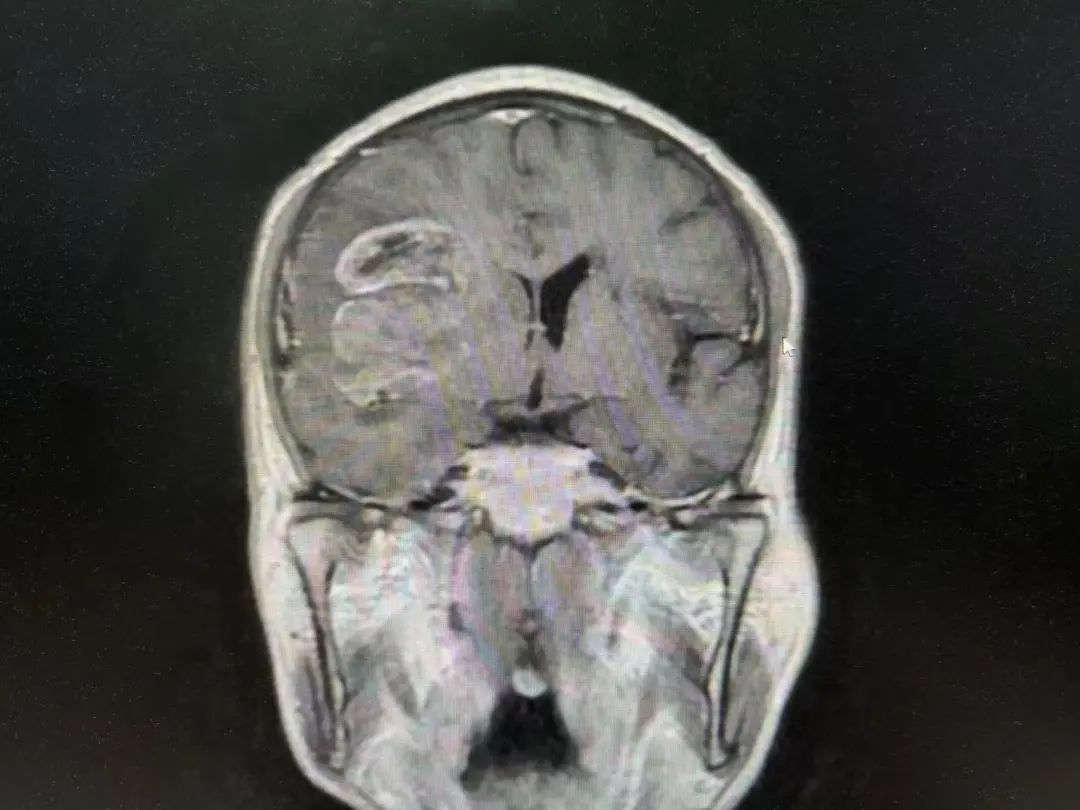

男性 | 67歲

主訴:左側(cè)口角流涎10天,左側(cè)肢體無(wú)力7天。

MR:右側(cè)大腦半球腫瘤性病變,考慮高級(jí)別膠質(zhì)瘤(大者大小約3.8cmx4.6cmx3.4cm)。